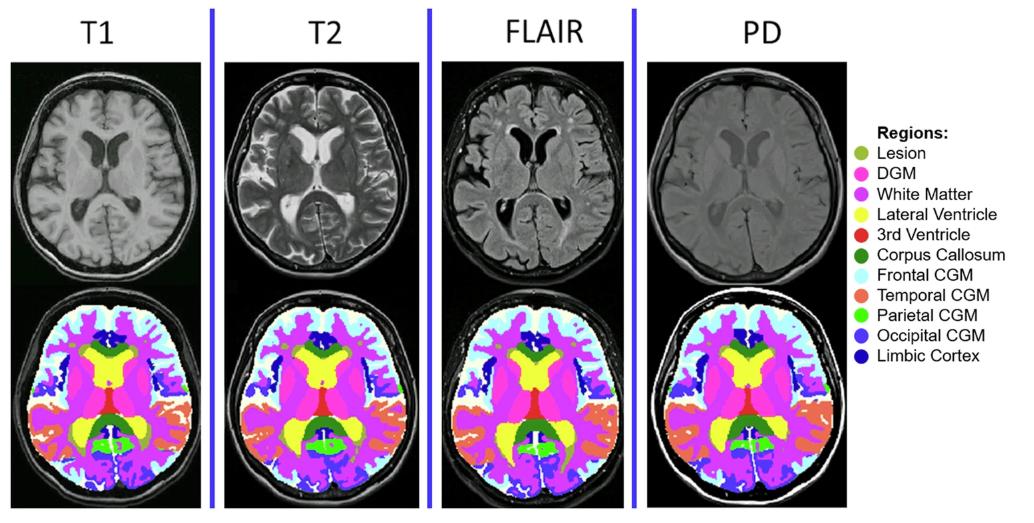

*MindGlide 通过医院档案中常用的 MRI 对比和相关组织强度(T1-weighted、TI-weighted、Proton Density (PD) 和 T2-Fluid Attenuated Inversion Recovery (FLAIR))处理 MRI,包括 2D 和 3D 扫描。

在检测脑组织损失的治疗效果中,MindGlide 显示了治疗组皮质 GM 体积损失率明显低于安慰剂组。下图为各种对比的分割示例。